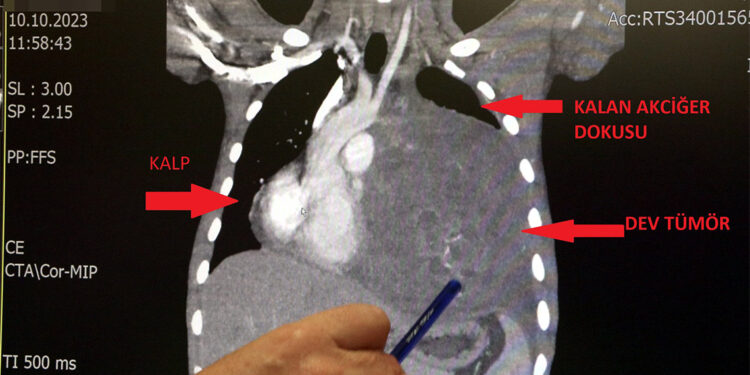

Sol akciğerinin yüzde seksenini kağıt gibi ezen, kalbini göğüs duvarında 12 santim sağa kaydıran ve hem kalbe hem beyne giden ana damarlara baskı yapan 6.5 kilo ağırlığındaki dev tümör, Koşuyolu Yüksek İhtisas Eğitim ve Araştırma Hastanesi Göğüs ve Kalp Damar Cerrahisi ekiplerinin birlikte girdiği operasyonla başarılı şekilde çıkarıldı. Operasyon sırasında Aktaş’ın kalbi normal yerine çekildi, sol akciğerin üst lobu alındı, ezilen alt lobu ise anestezi ekipleri tarafından pozitif basınçla yeniden şişirildi. Ameliyatı gerçekleştiren ekipten Prof. Dr. Erdal Taşçı, Aktaş’ın göğüs boşluğunun neredeyse tamamını kaplayan 6,5 kiloluk tümörün teratom (eski Yunancada ‘canavar tümör’) türlerinden biri olduğunu ve embriyonik hücrelerden kaynaklandığını kaydetti.

Prof. Dr. Erdal Taşçı, “Bundan 2,5-3 ay öncesine kadar hiçbir problemi olmayan, hayatını normal devam ettiren bir delikanlı Burak. Göğüs ağrısı öksürük ve nefes darlığı şikayetiyle sağlık kuruluşuna başvuruyor. Orada yapılan tetkiklerinde sol göğüs boşluğunda akciğerinden kaynaklanmayan portakal büyüklüğünde bir kitle tespit ediliyor ve immatür teratom tanısı konuyor. 2 ay arayla yapılan tetkiklerinde ve arada cerrahi öncesi küçültme amaçlı kemoterapi almasına rağmen, portakal büyüklüğündeki tümör, irice bir karpuz büyüklüğüne, yaklaşık 6 kilo 300 grama kadar ulaşıyor.

Göğüs boşluğunda kemik kafesi içinde olduğu için, itebileceği iki organ var; biri kalp, diğeri de akciğerler. Soldan sağa doğru büyüdüğü için kalbi tamamen göğüs boşluğunun sağ tarafına itmiş ve kalbe giren ve kalpten çıkan bütün büyük damarları da yer değiştirmenin etkisiyle bükülmüş durumdaydı. Bu nedenle vücuduna yeterince kan gitmiyordu. Ağustos ayının başında portakal büyüklüğündeyken kitle Eylül sonuna irice bir kavun, Ekim ayına geldiğimizde ise bir karpuz büyüklüğüne ulaştığı için, kitlenin büyüme hızı bizi acilen ameliyat yapmaya yöneltti. Yaklaşık 8-10 kat hacimsel olarak artmıştı.

Normalde kalbin özellikle alt ucunun göğüs boşluğunda, iman tahtası orta çizgi kabul edilirse, sola bakar şekilde durduğuna dikkat çeken Prof. Dr. Taşçı, sözlerini şöyle sürdürdü: “Ama bu hastada yaklaşık 12-13 s santimlik kalbin alt ucununu yer değiştirmesi ve kalbe giren çıkan bütün damarlar bükülüp kan akımı bozulmuştu. Kalp Damar Cerrahisi ekibi de bizimle beraber ameliyata girdi. Sol akciğerin üst lobu artık geri dönüşümsüz olarak ezildiği için çıkarmak zorunda kaldık. Kalbi tekrar eski pozisyonuna getirdik.